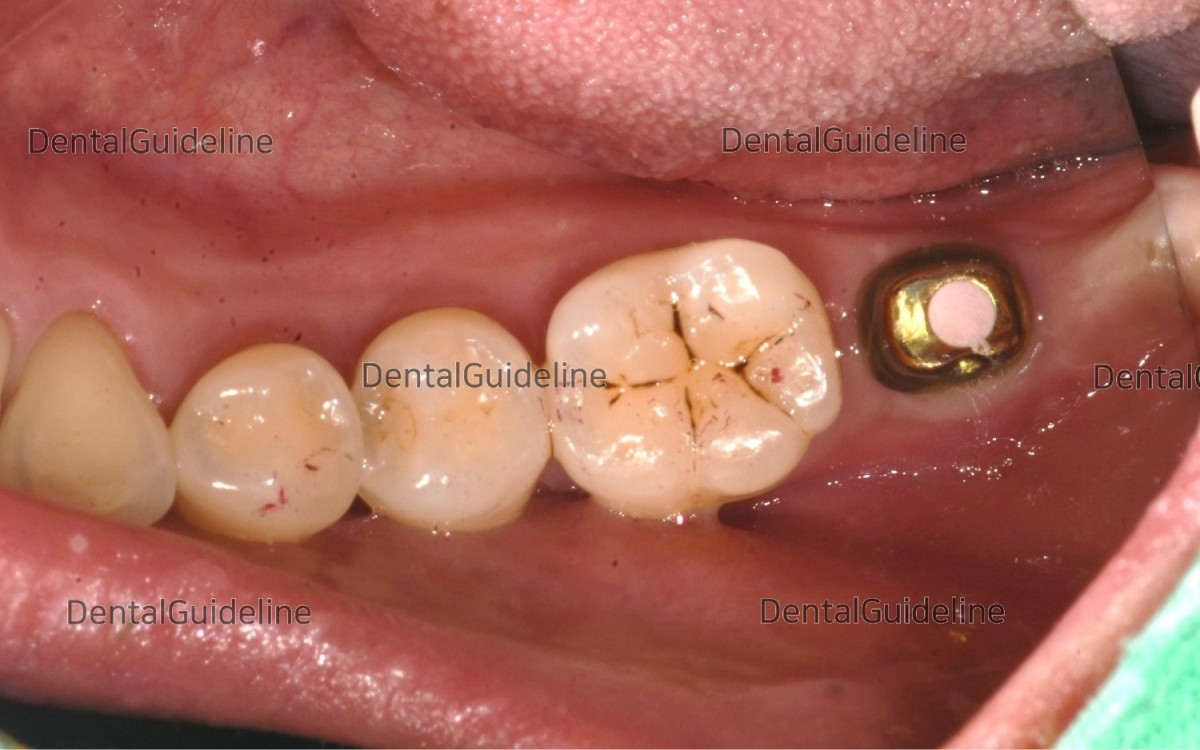

14. Intraoral photo on the day of impression taking.

15. A customized abutment was connected to the fixture according to recommended torque value and the screw hole was filled with a temporary filling material.

16. The opposing tooth was restored with a crown.

17. The occlusal adjustment was done and the access hole on the crown was filled with composite resin.